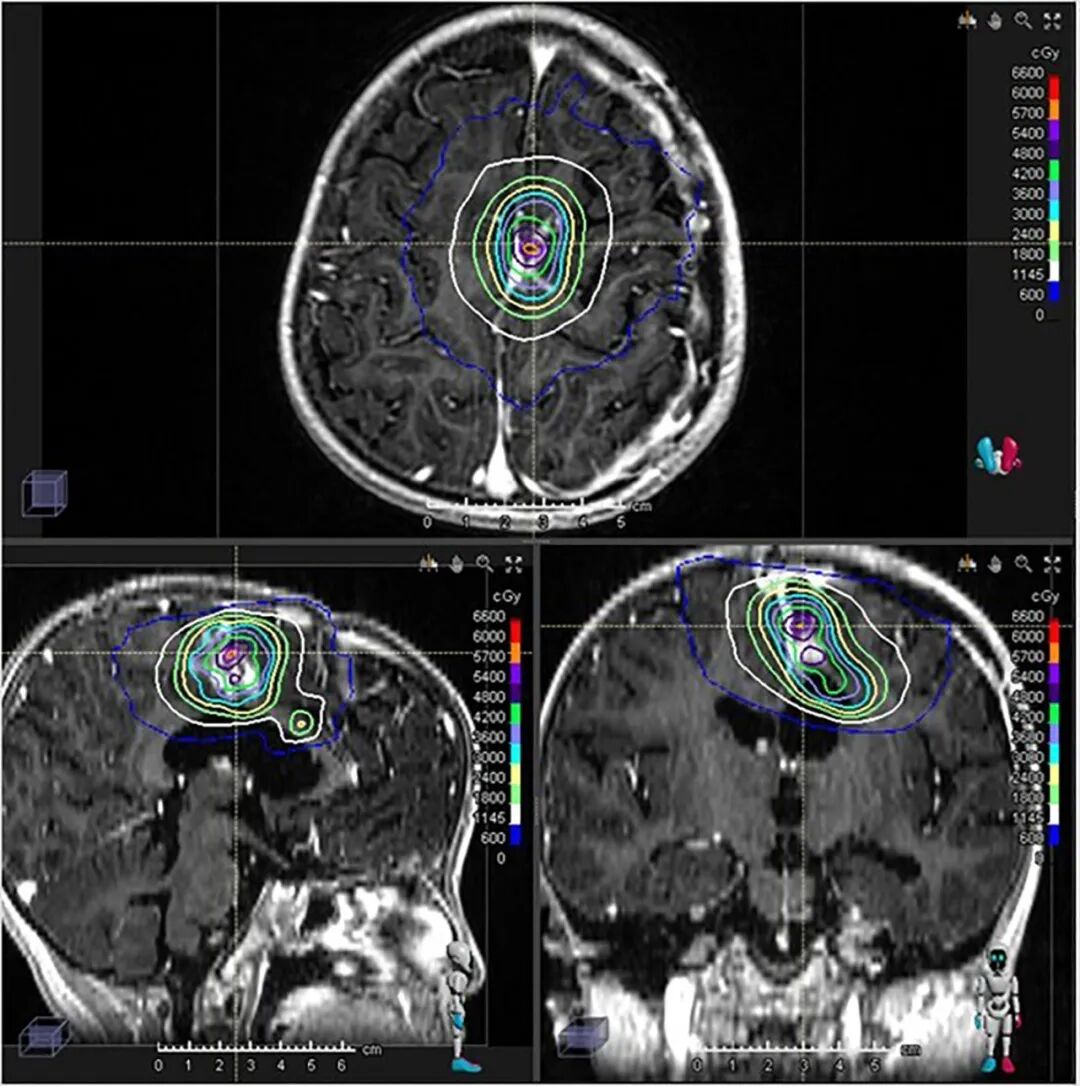

在为患儿进行了大范围的安全手术切除后,治疗团队选择了医院的质子治疗(PBT)进行术后辅助放疗。质子治疗凭借其独特的“布拉格峰”物理优势,能够将放射剂量精准集中在肿瘤区域,同时最大限度地保护周围的正常脑组织。这一步不仅是精准的初步治疗,更是一次极具远见的“布局”——通过减少对健康组织的损伤,为后续可能需要的再次放疗保留了宝贵的“窗口期”。

第二步:“伽马刀”精准“收官”,完成最后一击

质子治疗后,团队曾采用靶向药物治疗以稳定病情。由于仍有少量肿瘤残留,在进行二次手术后,团队果断启用伽马刀(GKRS)进行“最后一击”。正是得益于前期质子治疗对周围正常组织的良好保护,才使得后续高剂量的、高度聚焦的伽马刀治疗得以安全、有效实施,最终对残余病灶进行了彻底处理。